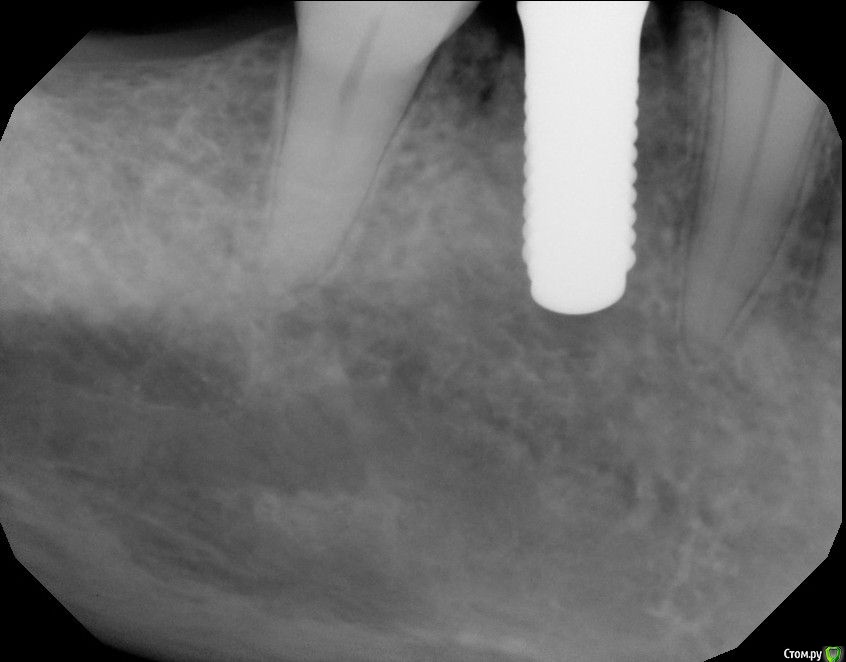

Astronaft Опубликовано 25 января, 2021 Автор Поделиться Опубликовано 25 января, 2021 Спасибо.День операции, 12 недель, день цементировки. 3 1 Ссылка на комментарий

Astronaft Опубликовано 24 января, 2021 Поделиться Опубликовано 24 января, 2021 (изменено) Одиночный цирнокиевый имплантат и расщепление без графта. Пациентка:тонкая хрупкая женщина 55 лет, сконцентрированная на своем здоровье, в некоторой мере мнительная.всегда тяжелые заживления после удалений (по опросам)есть результаты Клиффорд теста (такая книжка под 200 страниц с in vitro аллерго-пробами на все известные материалы) Поставленная цель:только цирконий Мне было интересно найти вариант найболее приемленый пациентке и мне. С минимом хирургического риска и риском сожаления пациентки про выбор костного материала. Во-первых, я не использую аллографты - философски, чужие протеины, неприятный запах - просто основываясь на своем мнении.Во-вторых, мнительные пациенты склонны "пойти и почитать" до или потом и как следствие внушить себе вещи которых может и не было. Но по скольку мысль материальна... Все обсудил заранее.План: ридж сплит (расщепление), имплантат без графта, свободный СТ графт; если случается вестибулярная рецессия - пилим зирконий во рту. Ридж сплит сделан пьезотомом - крестальный и вертикальные пропилы на глубины около 8-10мм.Пилотное сверло.Развдвинул кость остеотомами от 1.6мм до 3.5мм в диаметре.Очень мягкая кость - напомнила мегкую максиллу плотности ногтевой пластинки вестибулярно.Имплант встал легко, но торк 40нсм. СТ графт из области 18. Деэпителизирую скальпелем уже потом. Тут интересно отметить, что я перестал боятся ошметков эпителия.Пончо сверху имплантата (а-ля шашлык Карлоса).Швы. PTFE всегда хорош. 12 недель.Красивая десна.Периотест -5.8 - отличный результат.Оттиск. Циркониевая коронка симметричная другой стороне. Изменено 24 января, 2021 пользователем Astronaft 19 Ссылка на комментарий